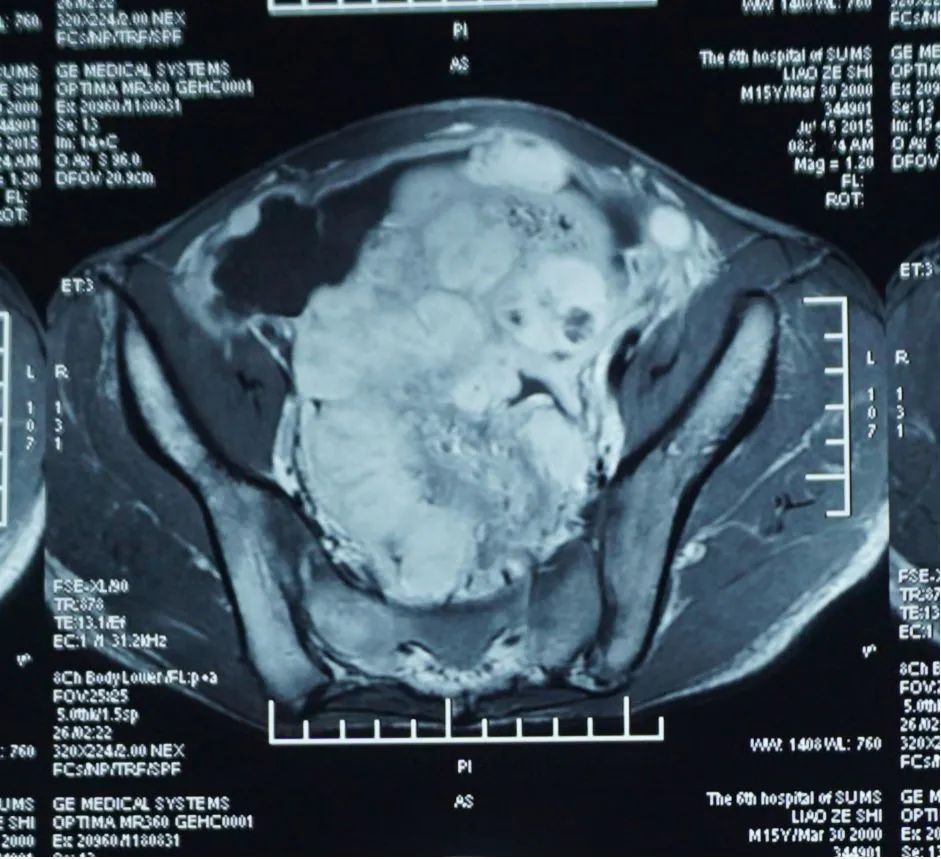

廖某,男,15岁。发现腹腔、盆腔多发肿块1月余。2015年7月29日入院。

2015-6月起患者无明显诱因出现持续腹泻,每日大便约10-20次,呈水样便,伴腹胀。当地医院CT:中下腹及盆腔多发肿物;肿物穿刺活检:上皮样炎性肌纤维母细胞瘤。

三凹征(+),腹部膨隆,叩诊呈鼓音,中下腹部可扪及一约6cm*5cm大小肿物,质硬,肝脾无肿大,肛周有赘生物,肛周有鲜血渗出。

腹、盆腔炎症肌纤维母细胞瘤(Ⅳ期)

起病时